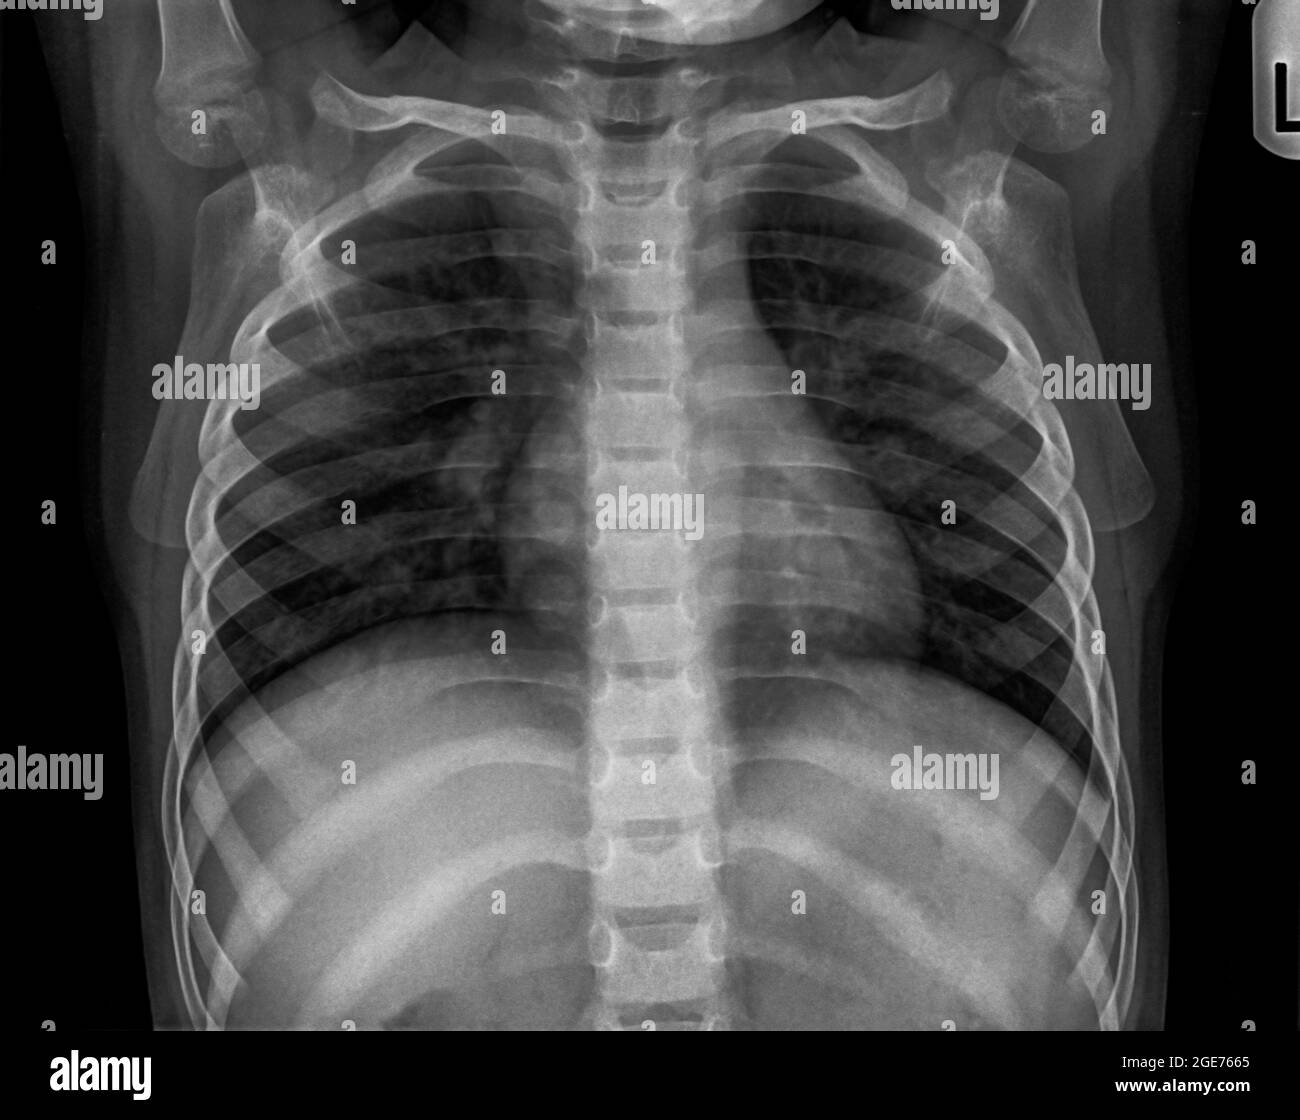

baby chest x ray pneumonia

Pneumonia In Children Intechopen

. The one that our children catch at school or from family members of mild to moderate severity does not result in complications. Review Of Baby Chest X Ray Pneumonia 2022. When the chest radiograph also includes the abdomen look out for the.

7 if a child. There is a problem with. Video will describe how pneumonia may look like on a chest x-ray.

Diagnosis Of Other Lung Conditions In Premature Babies

Neonatal Pneumonia Imaging Practice Essentials Radiography Computed Tomography

An Infant With Pneumonia Failure To Thrive And Persistent Radiographical Changes European Respiratory Society